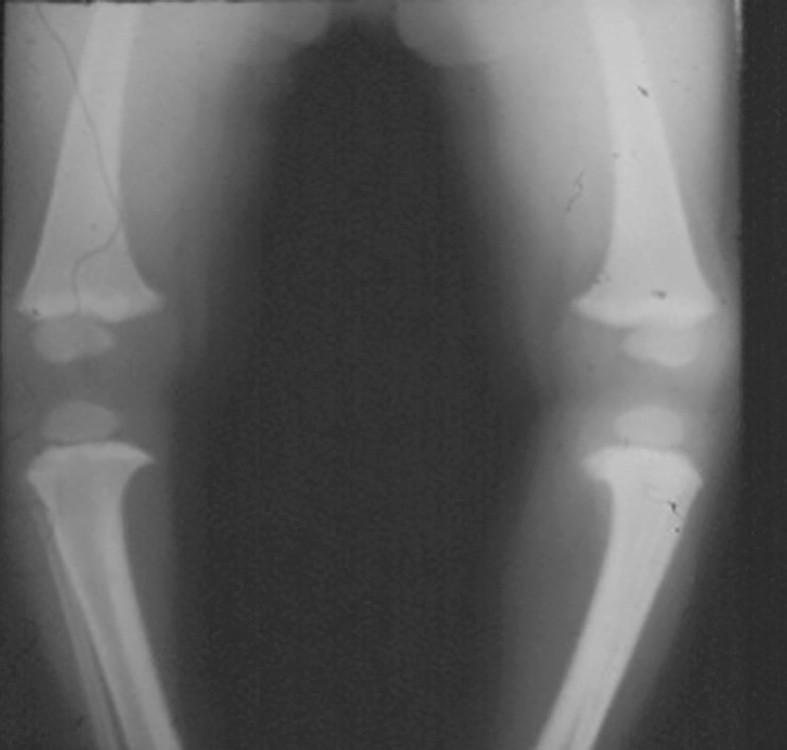

Il ginocchio valgo dell’infanzia è molto più comune rispetto al ginocchio varo, si presenta generalmente intorno ai 3 anni di età, in forma bilaterale ed è asintomatico. La patogenesi, analogamente al ginocchio varo dell’infanzia, sembra correlata ad un transitorio alterato ritmo di crescita delle cartilagini di accrescimento del ginocchio, anche se in questi casi viene soprattutto interessata la cartilagine distale del femore. In questo caso la porzione mediale è più attiva rispetto a quella laterale. Clinicamente è presente un incremento della distanza intermalleolare interna più o meno evidente a livello delle caviglie e viene valutata in centimetri (Fig. 6).

La procedura chirurgica correttiva, da effettuare nei casi persistenti, nelle forme adolescenziali e nei casi secondari ad altre patologie (come ad esempio affezioni genetiche, displasie ossee o patologie dismetaboliche (Fig. 7), prevede una emiepifisiodesi delle cartilagini di accrescimento coinvolte mediante placche a 8, allo scopo di bloccare l’accrescimento della cartilagine interna distale dell’osso e/0 prossimale della tibia e favorire il riallineamento del segmento scheletrico10 (Fig. 8).